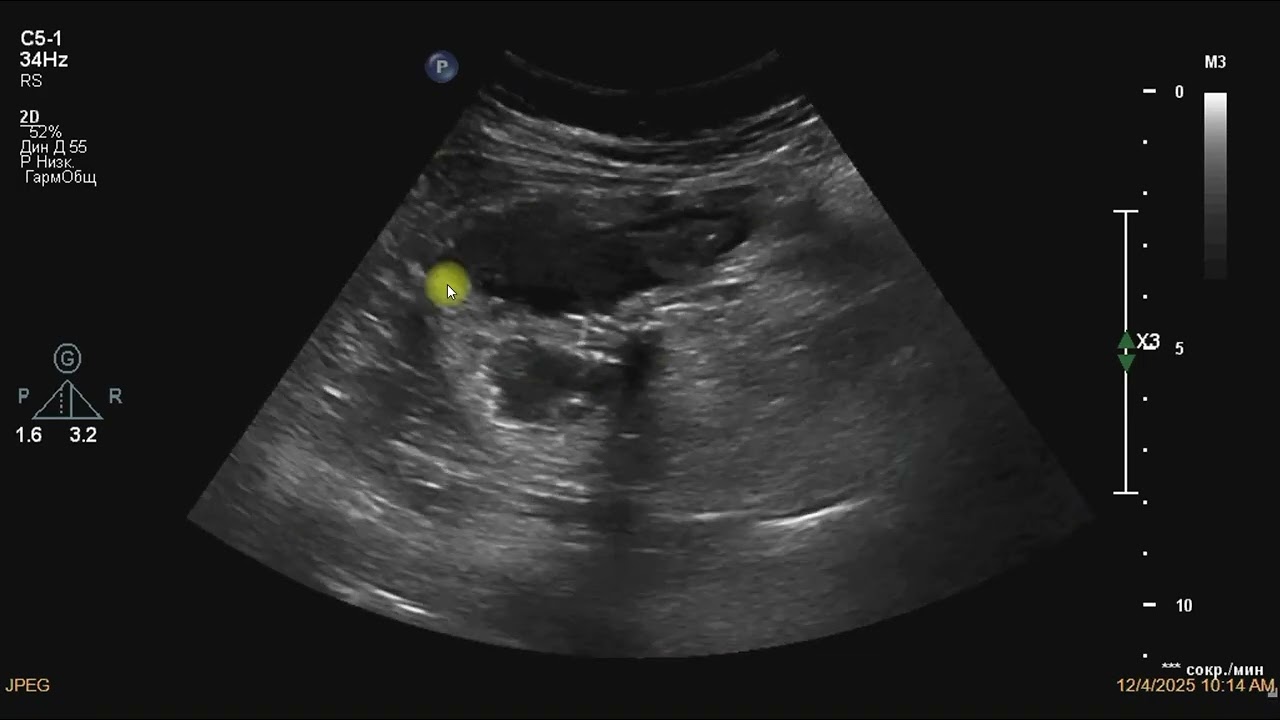

В правой подвздошной области, в проекции илеоцекального перехода, определяется стенозирующее опухолевое образование, вовлекающее купол слепой кишки, баугиниеву заслонку и терминальный отдел подвздошной кишки.

Купол слепой кишки: стенка с локальным нарушением слоистой дифференцировки, неравномерно утолщеная до 8–10 мм.

Баугиниева заслонка: не дифференцируется.

Терминальный отдел подвздошной кишки: стенка циркулярно утолщена до 8 мм, протяжённость поражения до 20 мм. В зоне поражения стенка гипоэхогенная, слоистость утрачена. Кровоток нерегулярный.

При компрессии датчиком область безболезненна, участок малосжимаем.

Просвет кишки в зоне илеоцекального перехода резко сужен до 1–2 мм. Определяется престенотическое расширение подвздошной кишки до 35 мм с усилением перистальтики.

Параколическая клетчатка в зоне поражения инфильтрирована, повышенной эхогенности.

Наружные контуры слепой и подвздошной кишки в области поражения неровные, размытые - признаки опухолевой инфильтрации.

Паракавально визуализируются увеличенные лимфатические узлы до 20 мм, округлой формы, с периферическим кровотоком.

По ходу гепатодуоденальной связки — несколько гипоэхогенных округлых лимфоузлов до 15 мм, аваскулярных.

В паренхиме печени определяются множественные гипоэхогенные очаговые образования размерами 10–23 мм, с перинодулярной васкуляризацией при ангиосканировании.

Эхографическая картина стенозирующей опухоли илеоцекального перехода с вовлечением купола слепой кишки, баугиниевой заслонки и терминального отдела подвздошной кишки и формированием частичной кишечной непроходимости.

Признаки местного опухолевого распространения.

Забрюшинная и гепатодуоденальная лимфоаденопатия (mts)

Вторичное очаговое поражения печени (mts).